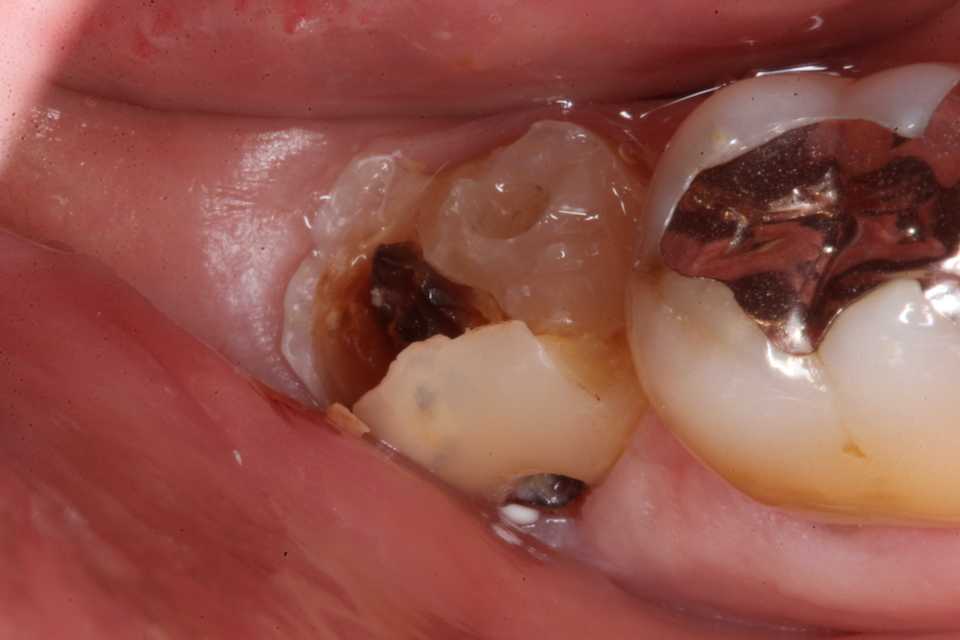

ストリップスを使わない隣接面CR(ダイレ… 2025.11.26

ストリップスを使わない隣接面CR(ダイレ… 2025.11.07